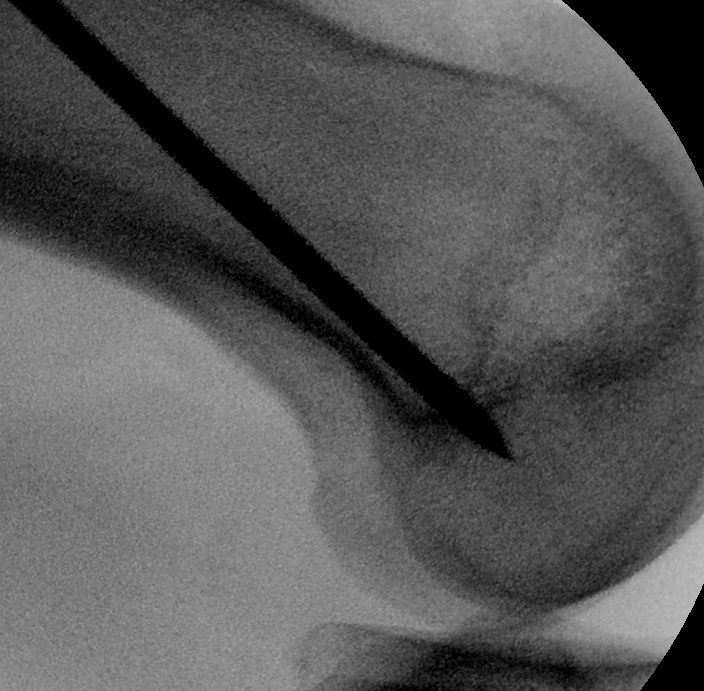

- II with perfect lateral of knee

- superimposed femoral condyles

- check entry on lateral

- imagine posterior femoral condyle as circle

- entry point in centre, but 60% of distance posterior

- can also look inside knee with scope to confirm insertion